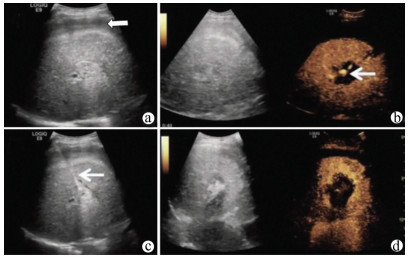

肝病超声诊断指南

中华医学会超声医学分会, 中国研究型医院学会肿瘤介入专业委员会, 国家卫生和健康委员会能力建设和继续教育中心超声医学专家委员会

2021, 37(8): 1770-1785. DOI: 10.3969/j.issn.1001-5256.2021.08.007

超声检查无创、实时、价廉,无辐射、便于反复进行,是最常用的肝脏影像学检查方法。近年来,超声检查新技术如超声造影、弹性成像发展迅速,可有效鉴别肝内占位性病变性质、评估肝纤维化和门静脉高压程度以及监测肝病治疗效果,在临床肝病及其介入治疗中发挥重要诊断价值。本指南规范了肝病多模态超声技术(灰阶超声、彩色多普勒超声、超声造影、弹性超声)检查的仪器调置、患者准备及医生检查方法;对肝脏弥漫性病变(炎性病变、纤维化、硬化)、多种占位性病变及肝病介入操作的多模态超声技术诊断标准进行了定义和规范,同时推荐了超声监测周期及肝脏疾病超声诊断报告书写规范。